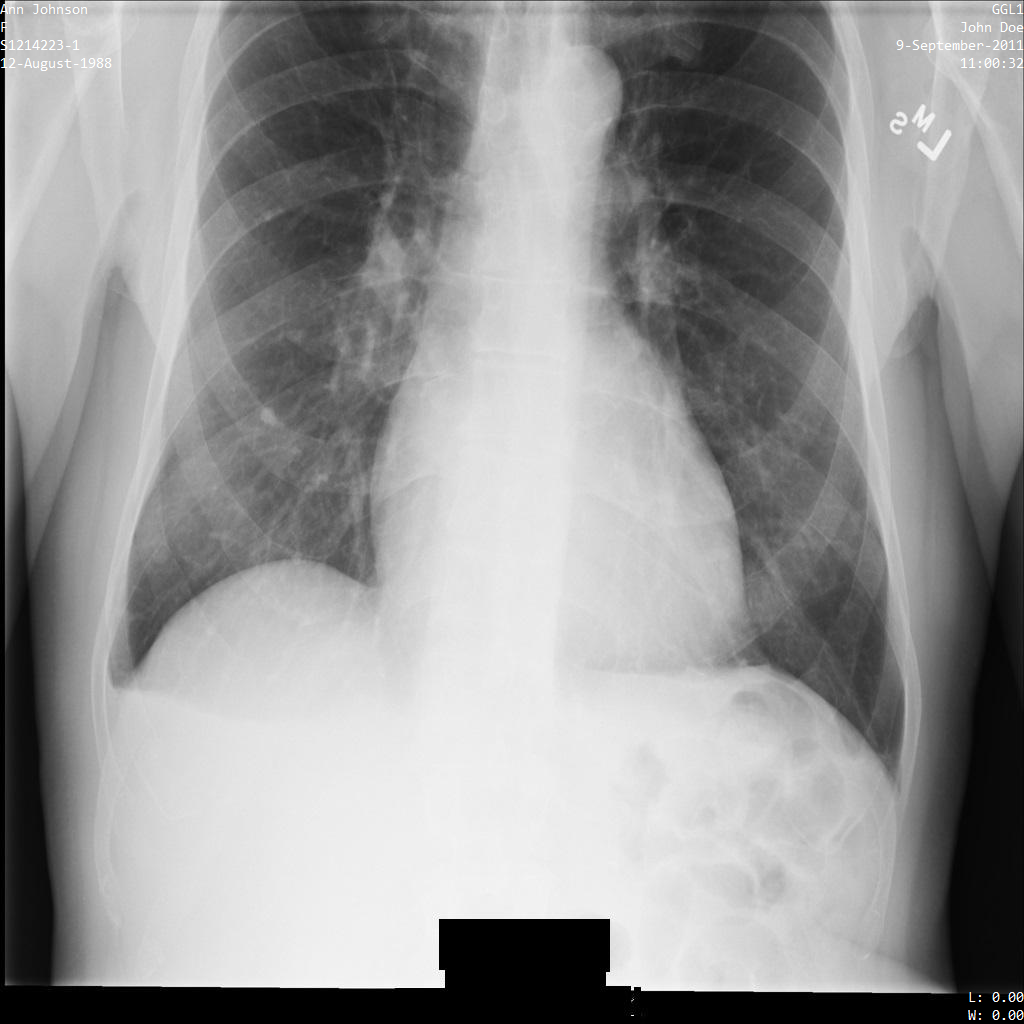

Depois de enviar a imagem para a Cloud Healthcare API através do perfil de filtro de etiquetas ATTRIBUTE_CONFIDENTIALITY_BASIC_PROFILE, a imagem é apresentada da seguinte forma. Embora os metadados apresentados nos cantos superiores da imagem tenham sido ocultados, as IPH incorporadas na parte inferior da imagem permanecem.

Para remover também o texto incorporado, consulte o artigo

Ocultar texto incorporado em imagens.